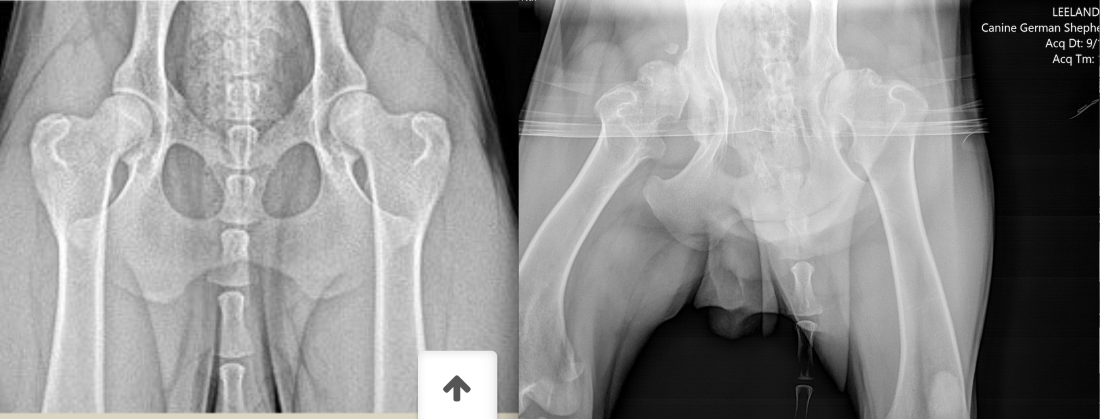

My new Moms noticed I didn’t travel the stairs confidently and my back swayed when I walked. They took me to see Dr. Kim who gave me some zen pills so she could take pictures of my back, pelvis and knees. After reviewing the pictures we learned I had Severe Bi-Lateral Hip Dysplasia. Dr. Kim recommended we see a surgeon in Canada to discuss my options. Dr. Karen took a look at my slides and said it was the worst dysplasia she had ever seen. Needless to say, everyone agreed that I should start taking anti-inflamitory drugs. I don’t mind the drugs–they taste like liver and I’m able to run around a little now!

Here’s a side by side view of normal hips and my hips: